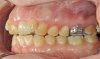

Das Quietschen fällt mir schon gar nicht mehr auf. Aber ich trage sie weiterhin fleißig. Ich kann schon sagen, dass sich der Zahn, gut eingestellt hat. Vor vier Monaten konnte ich noch die Kaufläche mit meiner Zunge beim zubeißen erfühlen. Das geht jetzt nicht mehr. Ich schaue mal, ob ich gleich noch die Fotos meiner KFO vor der Behandlung und von vier Wochen hochladen kann. Da kann man den Unterschied schon gut erkennen. Was ich als Laie halt so sagen kann. Außerdem habe ich das Gefühl, dass mein rechter vorderer Eckzahn etwas mehr Platz hat und nicht mehr so weit nach vorne steht.

Okklusion_rechts-Anfangsdiagnostik-2023_09_20-0_2[1].jpg Okklusion_Anterior-Anfangsdiagnostik-2023_09_20-0_1[2].jpg Okklusion_links-Anfangsdiagnostik-2023_09_20-0_3[1].jpg Okklusion_OK-Anfangsdiagnostik-2023_09_20-0_4[1].jpg Okklusion_UK-Anfangsdiagnostik-2023_09_20-0_5[1].jpg DSC_7646[1].JPG DSC_7649[1].JPG DSC_7651[1].JPG DSC_7652[1].JPG DSC_7655[1].JPG

Ich hoffe, ihr könnt auf diesen Bildern die Entwicklung sehen.